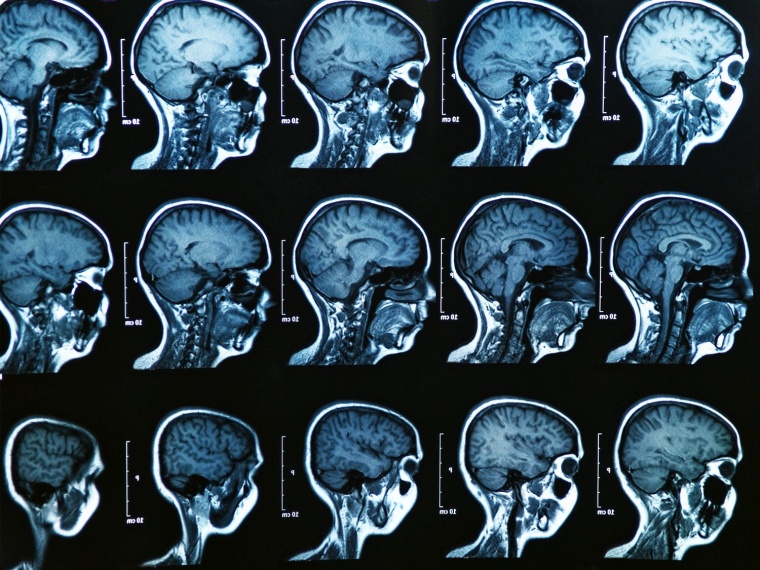

Rund 800 bis 1.000 dieser kleinen Drüsen sind im und um das Gewebe der Schleimhaut von Lippen, Mundhöhle, Nase und dem Mittelohr in unterschiedlicher Dichte verteilt. In der Regel sind sie nicht sichtbar und auch eine konventionelle Bildgebung ist nicht in der Lage, diese Drüsen darzustellen. Auffällig werden sie nur im Fall einer Erkrankung, beispielsweise bei Tumoren oder Zysten, die wiederum im Nasen-Rachen-Raum äußerst selten auftreten.